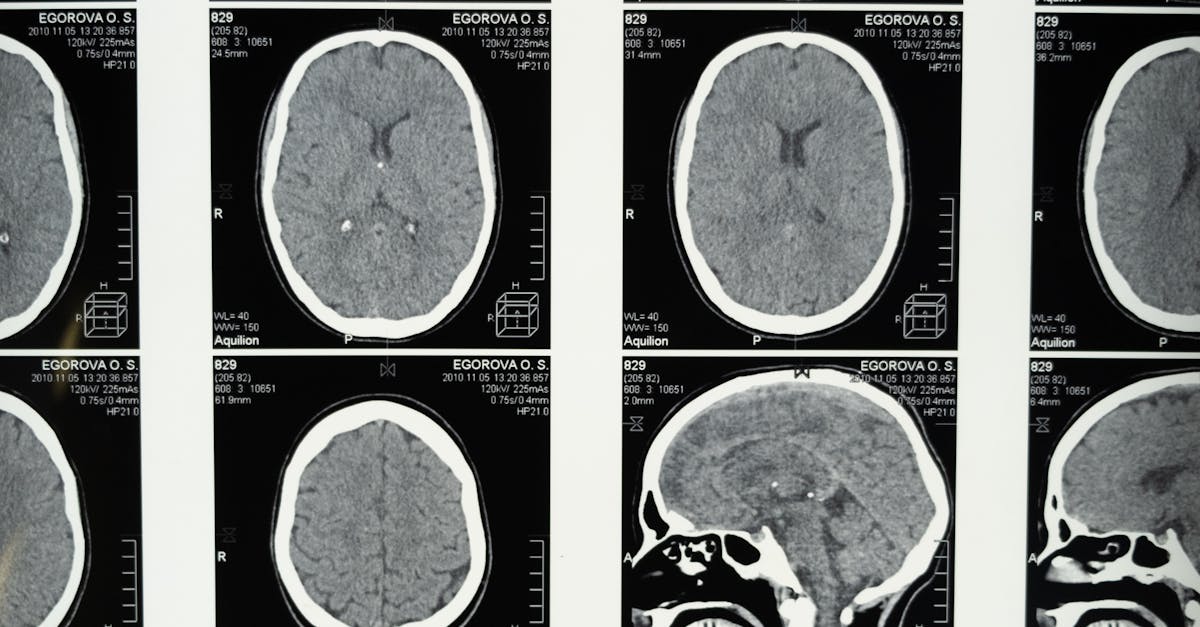

Common types of medical imaging techniques include X-rays, ultrasound, computed tomography (CT), magnetic resonance imaging (MRI), and nuclear medicine imaging such as positron emission tomography (PET) scans.